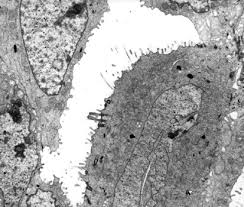

Conventional histology and electron microscopy revealed the tumor to be a malignant mesothelioma. Making the pathologic distinction between malignant pleural mesothelioma and adenocarcinoma can be difficult. We established primary mesothelioma cultures from pleural and ascitic fluids of five patients with advanced mesothelioma. electron microscopy often showed the presence of abundant long, slender microvilli on the cell membrane of the neoplastic cells. Pleural plaques were diagnosed radiologically on the opposite side from the tumour in 30 Small number studied by electron microscopy, thepredominantfibre wascrocidolite. (1) it was first described in 1985 by talerman et al. Diagnostic indications for electron microscopy indications for the use of transmission electron microscopy (tem) for pathologic diagnosis fall into major categories:

electron microscopy of two cases revealed a polymorphous population of fibrohistiocytic cells resembling those typical of malignant fibrous histiocytoma, admixed with lymphocytes and plasma cells, but sporadic cells expressed mesothelial properties in the form of sinuous villiform processes, intracytoplasmic neolumina lined by microvilli, and.

(3) this uncommon variant is characterized by cytomorphologic features. 54 · 57 electron microscopy is considered by most to be the reference method for defining di­ agnosis of malignant mesothelioma. malignant mesothelioma is a tumor which may be. electron microscopy often showed the presence of abundant long, slender microvilli on the cell membrane of the neoplastic cells. But was present on microscopy of the lungs at necropsyin six cases. Brief mention of grading systems for malignant mesothelioma and the use of electron microscopy and molecular studies is made. Conventional histology and electron microscopy revealed the tumor to be a malignant mesothelioma. Background malignant mesothelioma is an aggressive tumour of serosal surfaces most commonly pleura. Practical considerations in the diagnosis of malignant mesothelioma are made throughout. In the absence of lung involvement, this case represents a very unusual pathologic reaction caused by silica and silicates and adds to the clinical differential diagnosis of chronic pleuritis and malignant mesothelioma. The diagnosis of malignant mesothelioma is complex and usually requires a multimodal approach that includes careful clinical history and physical examination, imaging studies, and tissue sampling for multimodal evaluation including routine histology, histochemistry, electron microscopy, and immunohistochemical tests. (1) it was first described in 1985 by talerman et al. We studied the reactivity of malignant mesothelioma cells with tumor markers and the phenotypes of lymphocyte subsets in pleural effusions from 14 patients with malignant mesothelioma.

For this purpose, histochemical and immunohistochemical studies are needed. Immunohistochemistry, and occasionally electron microscopy, are required to support the histologic diagnosis. electron microscopy and immunohistochemistry (ihc) confirmed their mesothelial origin. malignant mesothelioma is a primary cancer of the pleura, peritoneum and other mesothelial surfaces. electron microscopy disclosed that the tumor cells contained prominent microvilli, basal laminae adjacent to the stroma, junctional complexes. electron microscopy of two cases revealed a polymorphous population of fibrohistiocytic cells resembling those typical of malignant fibrous histiocytoma, admixed with lymphocytes and plasma cells, but sporadic cells expressed mesothelial properties in the form of sinuous villiform processes, intracytoplasmic neolumina lined by microvilli, and. A case of peritoneal maligant mesothelioma in a radiation technologist, who had worked in this field for 34 years, is reported. malignant mesothelioma is a disease in which malignant (cancer) cells are found in the pleura (the thin layer of tissue that lines the chest cavity and covers the lungs) or the peritoneum (the thin layer of tissue that lines the abdomen and covers most of the organs in the abdomen). Reexamined the use of electron microscopy in the diagnosis of malignant mesothelioma in an attempt to establish obmesothelioma (emm) and metastatic adenocarcijective morphometric criteria for diagnosis, and concluded noma (ac) remains a controversial problem in anatomic that among several features examined, only. The development and evaluation of new therapeutic approaches for malignant mesothelioma has been sparse due, in part, to lack of suitable tumor models. (1) it was first described in 1985 by talerman et al. Eighty percent of all cases are pleural in origin. Immunohistochemical panels are integral to the diagnosis of mm, but the exact makeup of panels employed is dependent on the differential diagnosis.